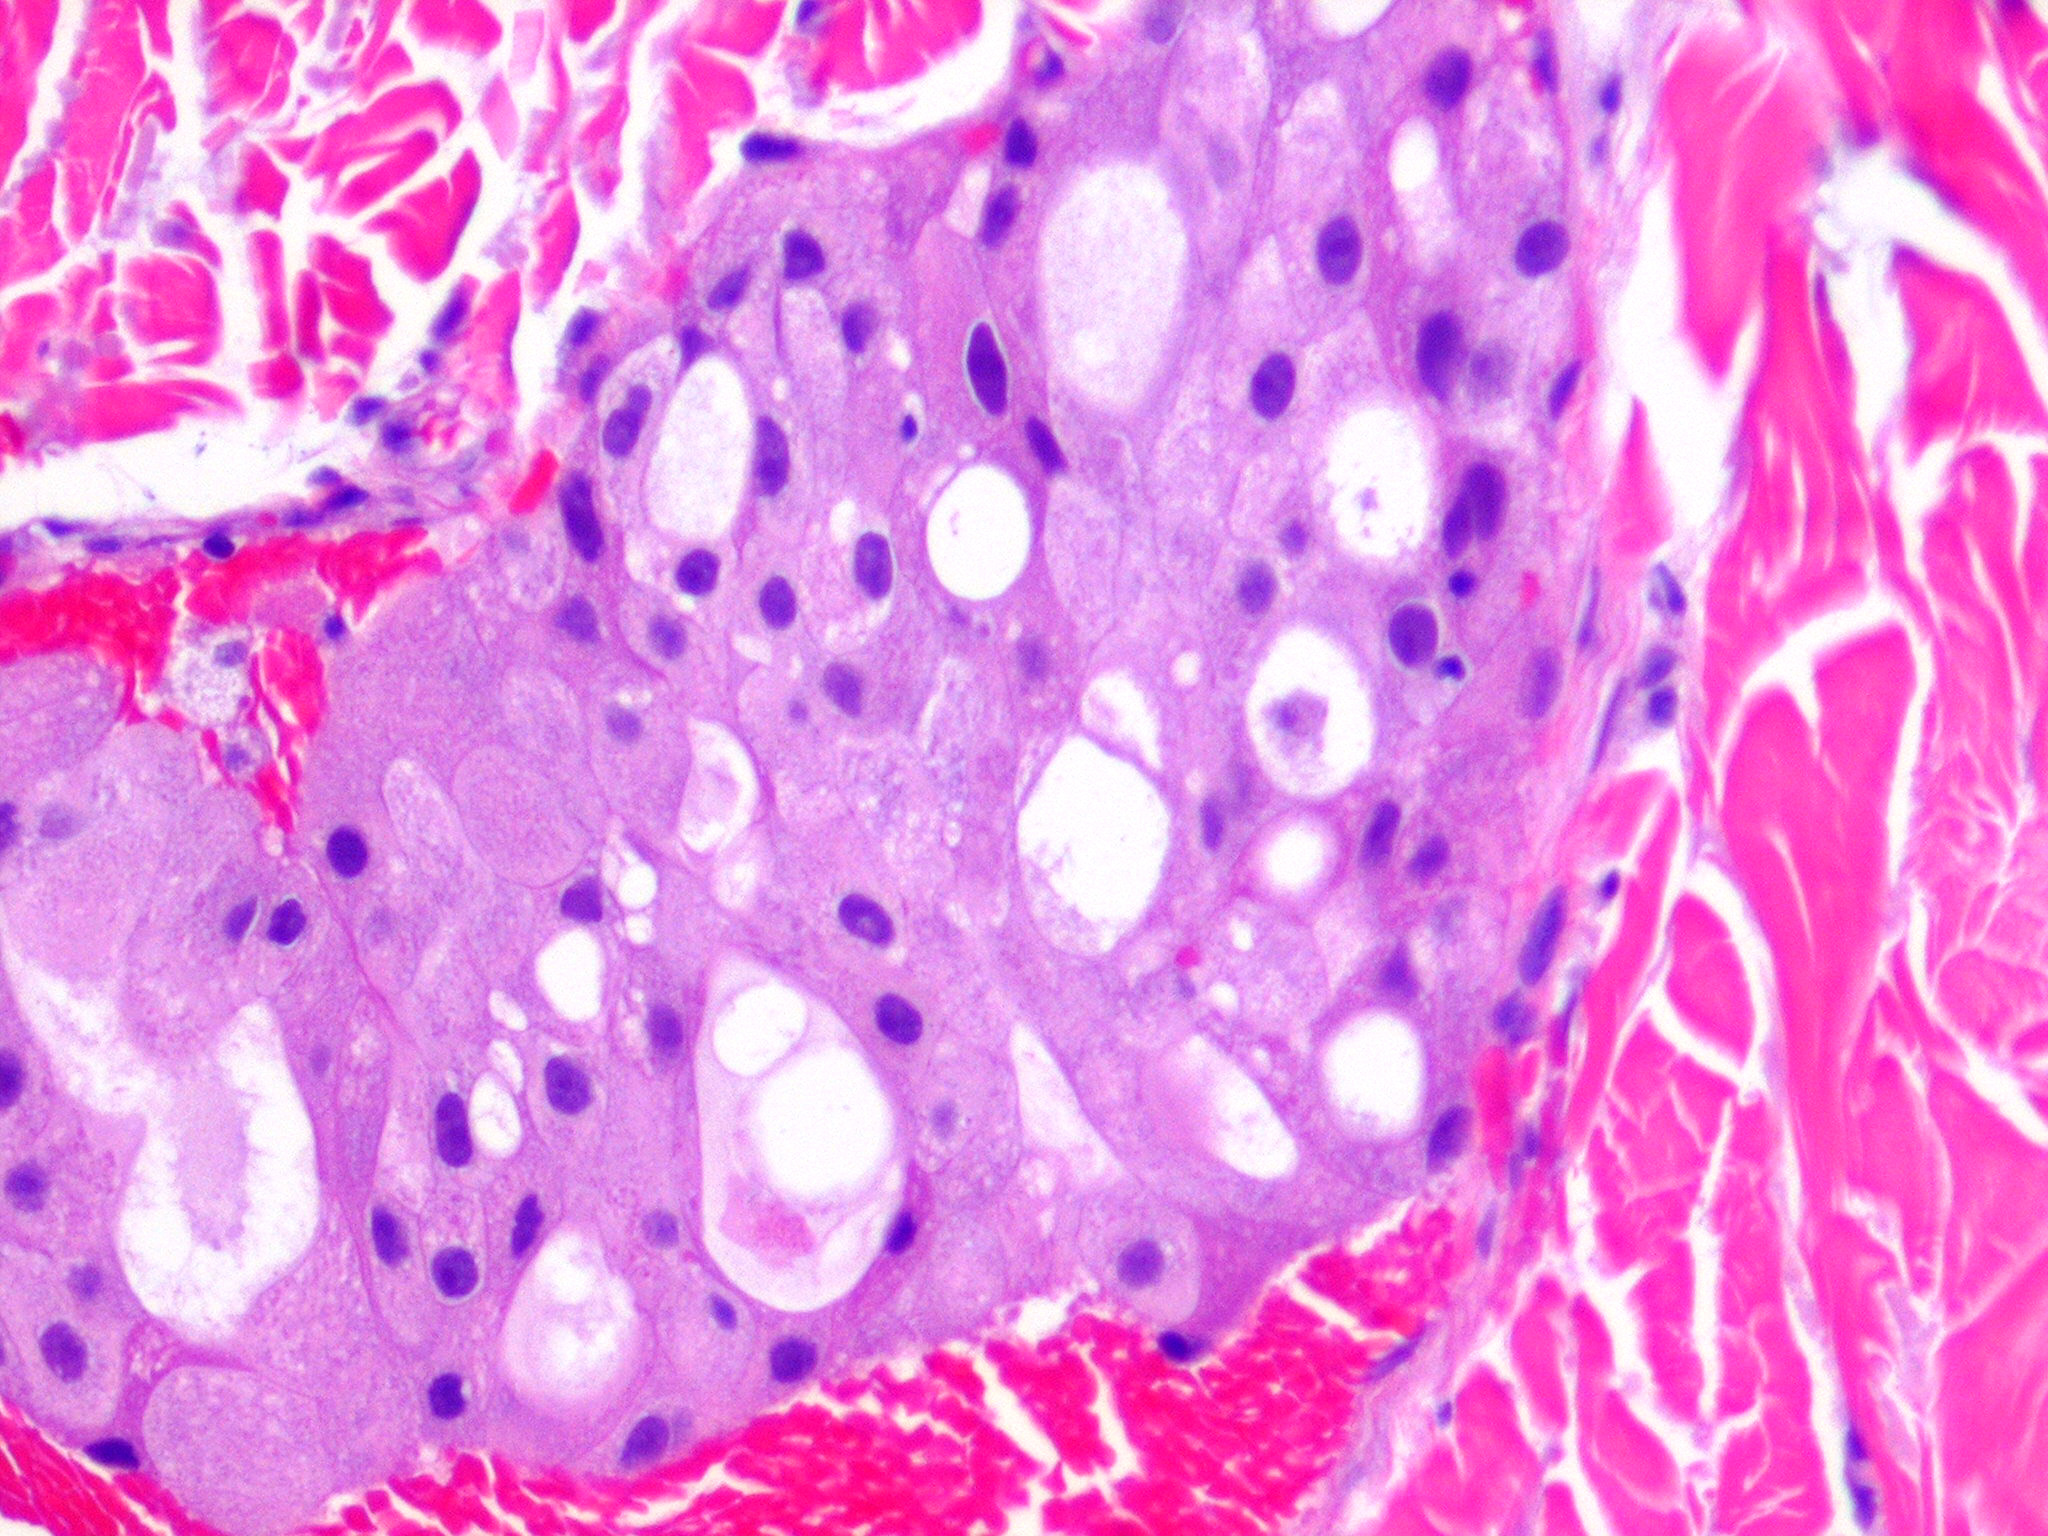

metastasis